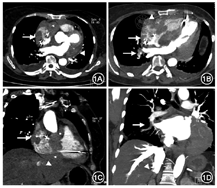

患者女性,64岁,因"反复胸闷,心悸10余天"于2018年8月28日入院。3月前因"三度房室传导阻滞"行永久性起搏器植入术,手术顺利。无吸毒史。体格检查:神志清楚,精神萎靡。颈静脉充盈,听诊两肺呼吸音减弱,未闻及干、湿性啰音。心前区无隆起,未触及震颤,心尖搏动在第五肋间左锁骨中线偏内0.5 cm处,心界略大,心率86次/min,律齐,胸骨左下缘闻及低调隆隆样舒张中晚期杂音,收缩期前增强。血压99/74 mmHg(1 mmHg=0.133 kPa)。实验室检查:D-二聚体4.43 mg/L,国际标准比值2.14,凝血酶原时间24.1 s,凝血酶原活性度60%,纤维蛋白(原)降解产物38.58 mg/L。心电图示:起搏器心律,VAT模式(超上限频率起搏器文氏方式传导);短阵房性心动过速。胸腹盆腔增强CT检查(图1)示:心影扩大,心包腔内、右心房内见多发不规则低密度肿块影,增强扫描肿块呈轻度强化。增强扫描动脉期图像显示心包内肿块包裹右冠状动脉及左冠状动脉回旋支部分节段;右心房近上腔静脉及下腔静脉入口区另见不规则无强化影;下腔静脉、肝右静脉分支内见逆流碘对比剂;右肺下叶肺动脉分支内见充盈缺损,未见明显强化。超声心动图(图2A、B)示:起搏器植入术后,右心房、左心室后壁房室沟、右心室侧壁及房室沟实性占位,伴三尖瓣机械性狭窄。临床术前诊断:右心房及心包腔多发肿瘤伴右心房血栓。于全身麻醉下建立体外循环支持,因下腔静脉解剖暴露困难,转自升主动脉、上腔静脉和右侧股静脉插管。术中探查所见:心包粘连严重,右心收缩较差,右心房为著。切开右心房可见近上腔静脉及下腔静脉入口区附着大量血栓,冠状静脉窦及三尖瓣附近见分叶状肿物突入右心房内,表面覆有炎性肉芽样组织,右房室口被肿瘤部分阻塞,三尖瓣活动受限未见受累。遂行右房肿瘤切除术+右房血栓清除术。切除右房内肿瘤及炎性肉芽样组织,清除右房内血栓。手术顺利。术后病理提示右心房肿瘤活检提示高侵袭性大B细胞淋巴瘤,符合Burkitt淋巴瘤(图2C)。免疫组织化学结果:肿瘤细胞CK(-),LCA(+),CD20(+),CD19(95%+),CD79a(+/-),CD3(T细胞+),CD10(小于5%),BCl-6(50%),MUM-1(70%),Ki-67(90%),C-MYC(60%),P53(++),BCL-2(60%),CD5(T细胞+)。肿瘤表面炎性肉芽肿样组织见大量多核巨细胞与密集的淋巴细胞浸润。术后患者接受抗凝治疗与CHOP方案(环磷酰胺+表柔比星+长春地辛+地塞米松)化疗。术后7周胸部CT显示心包内肿块较前显著缩小(图2D),症状已获得部分缓解。目前患者行周期性化疗中,一般状况良好。

本例患者术前增强CT图像具有一定特征性。CT图像显示心脏病变累及范围虽较为广泛,但心包内、右心房肿块强化呈轻度均匀强化,同时可见心包内轻度强化肿块包裹右冠状动脉及左冠状动脉回旋支的部分节段,呈血管淹没征象。血管淹没征象是淋巴瘤典型的影像表现之一。超声心动图及CT图像显示右心房三尖瓣口处的肿瘤术中证实单纯机械梗阻右房室口,未累及三尖瓣。而CT图像上近腔静脉开口区的不规则无强化影,手术证实为肿瘤导致的心房机械性梗阻而形成的附着于心房壁的血栓。本例肺动脉栓塞的栓子在增强CT上无明显强化,而瘤栓常出现不同程度强化,由此推测患者肺动脉内栓子更可能是脱落自右心房的单纯血栓。增强扫描动脉期碘对比剂逆流至下腔静脉、肝右静脉分支,Roth等[4]称此为"分支静脉对比剂淤积征",是心脏骤然停搏的CT增强表现[5],为右心房占位引起的右心房高压、右心房泵血功能不足所致。本病需与心脏血管肉瘤进行鉴别。心脏血管肉瘤通常比淋巴瘤更具侵袭性,累及心脏更大的范围,甚至穿透瓣膜、侵犯血管,同时在增强CT上趋向于显著强化,并常伴有坏死。